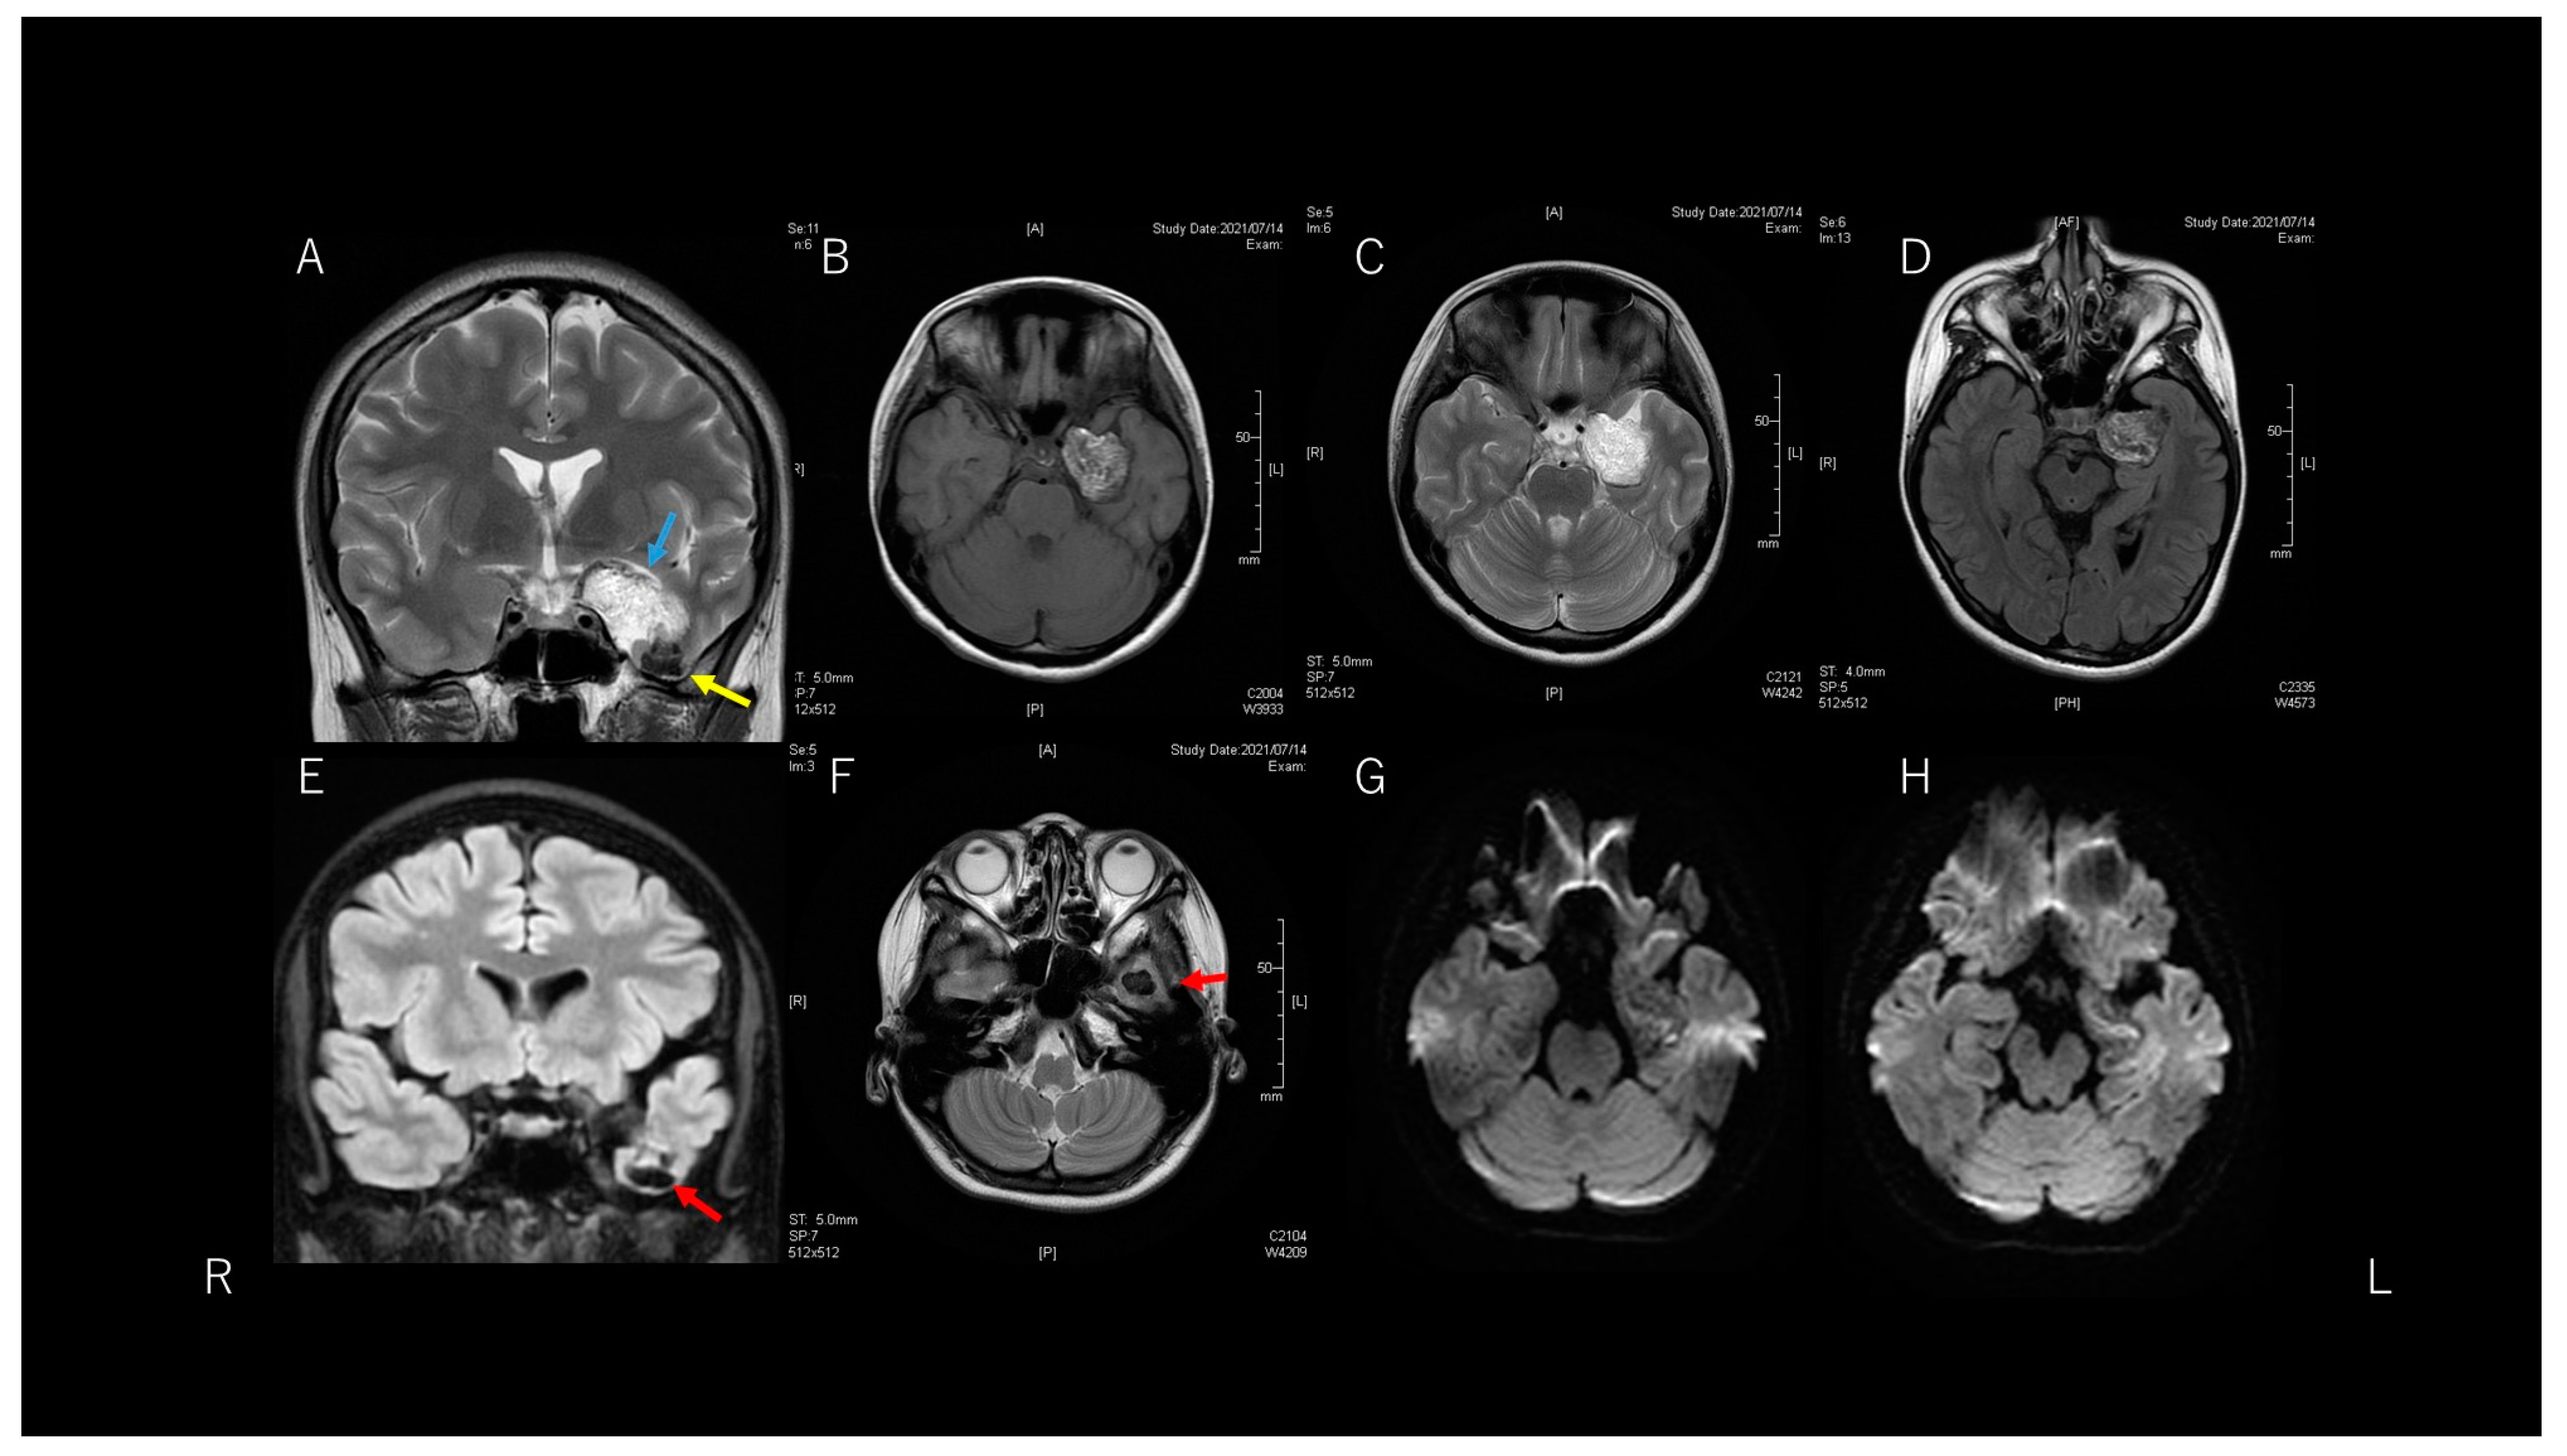

MRI (Figure 2) showed a well-delineated lesion in the left temporal lobe. The lesion had two major components. One component was mainly located in the medial temporal region and showed signal heterogeneity on T1-weighted imaging (WI) and hyperintensity on T2-WI. This massive component was displacing the left temporal lobe upwards and the hippocampus backward. This massive component was an extra-axial lesion, because T1-WI and fluid-attenuated inversion recovery (FLAIR) imaging showed a thin, hypointense space between the lesion and temporal lobe structures. The other component was a cystic part at the bottom of the temporal tip. This cystic part existed inside the temporal lobe. However, computed tomography showed a high-density lesion in the temporal tip, continuous with the massive medial temporal lesion. Diffusion-weighted imaging showed a low-intensity lesion with a slight hyperintense area inside the lesion.

Figure 2. A lesion is evident in the left temporal fossa. This lesion consists of two components, indicated by sky blue and yellow arrows (A). Axial T1-weighted imaging (WI) and T2-WI (B,C) show heterogeneous and hyperintense parts, respectively. Since a thin space exists between the lesion and temporal lobe structures, this component is considered an extra-axial lesion. This component is displacing the temporal lobe and hippocampus (D). The other component is located within the temporal lobe, appearing as a low-intensity cystic lesion (E,F: red arrows). Diffusion WI (G,H) shows heterogeneous, slightly hyperintense findings.